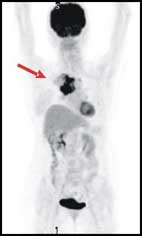

● 腫瘤細胞明顯增加代謝 (箭頭處)

PET/CT為結合正子掃描與電腦斷層的複合式掃描儀,除了用去氧葡萄糖來偵測體內高代謝腫瘤病灶的正子功能顯像外,更加上了電腦斷層掃描來精確結構定位。這兩種影像檢查各有擅場,互補後大幅提高診斷的準確與精確性。正子電腦斷層造影兼具安全無痛、大範圍全身檢查的優點,是近年來相當重要的醫學發明。